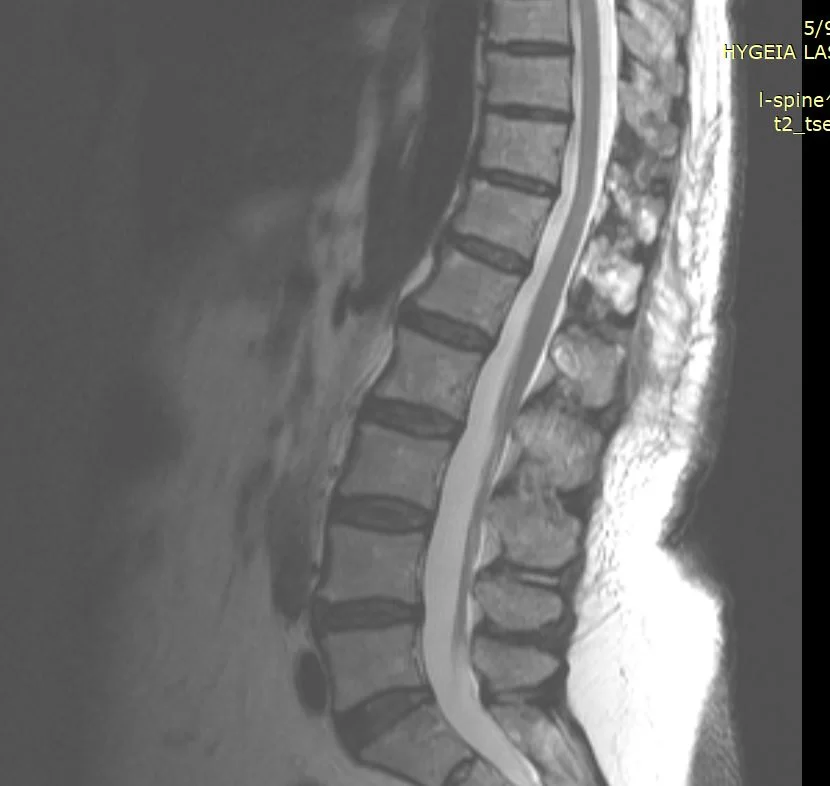

Ο έλεγχος με μαγνητική τομογραφία με σκιαγραφικό ανέδειξε μηνιγγίωμα όπισθεν του Θ12 σπονδύλου, με σημαντική πίεση επί των νευρικών στοιχείων.

Η μετεγχειρητική πορεία ήταν ανεπίπλεκτη με άμεση βελτίωση τόσο του πόνου όσο και της μυικής ισχύος και βάδισης της ασθενούς. Ο μετεγχειρητικός έλεγχος 3μήνου με μαγνητική τομογραφία αναδεικνύει την ολική εξαίρεση του μηνιγγιώματος αλλά και το εξαιρετικά περιορισμένο χειρουργικό τραύμα, λόγω της πεταλοπλαστικής.